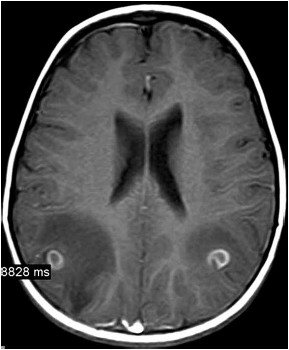

Homem de 45 anos apresenta o primeiro episódio na vida de convulsão focal seguida de generalização secundária. Não há comorbidade conhecida, trauma recente, febre ou algum sintoma sistêmico. Após o período ictal, a avaliação neurológica é normal. Não há febre e o exame físico não é contributivo. A ressonância magnética do encéfalo realizada é mostrada a seguir.

(Arquivo pessoal; imagem usada com autorização)

Considerando a principal hipótese diagnóstica, além de anticonvulsivante, a conduta inicial de escolha é